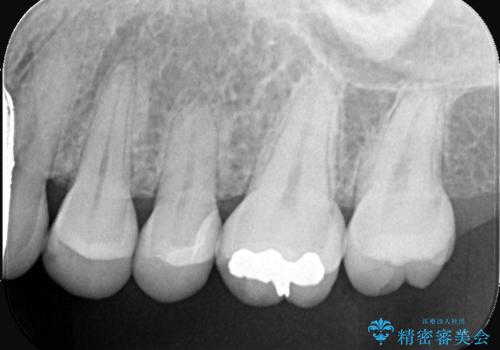

- クリーニング希望で来院されました。お口の中を確認したところ虫歯があり、部分的な詰めものでの修復となりました。材料の性質を説明し、セラミックインレーを選択されました。

接着時にはラバーダム防湿を行っています。